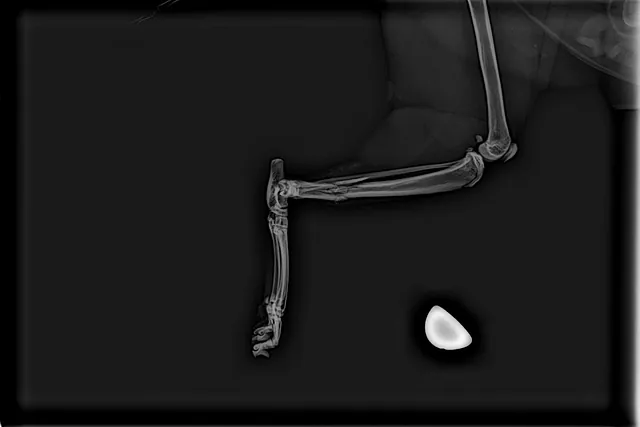

Imagerie

La clinique est équipée d'une radiographie numérique permettant au vétérinaire d'observer les tissus durs, comme les os, mais également divers organes thoraciques et abdominaux, tels que le cœur, l'estomac, la vessie, etc.